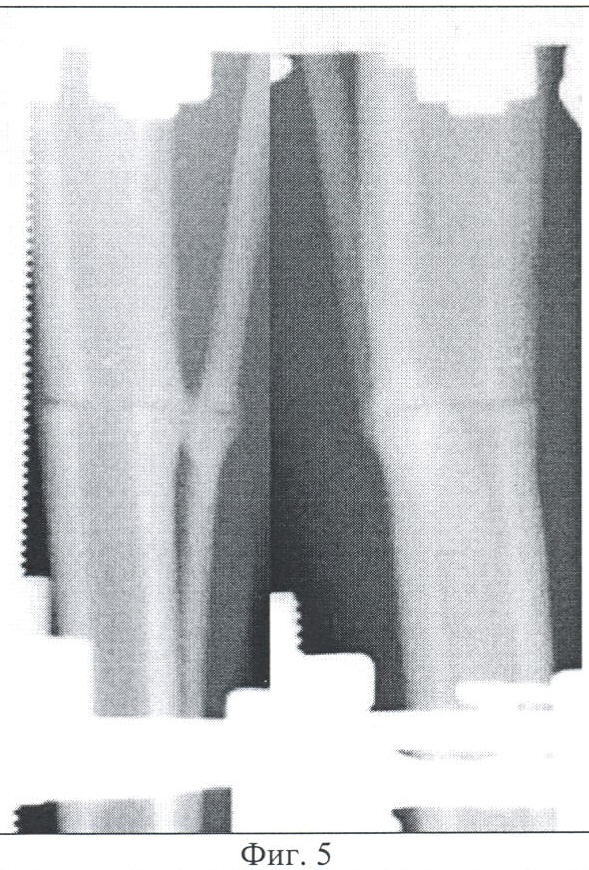

Фиг.3 – копия рентгенограммы костей голени согласно изобретению, конец дистракции.

Через 5 суток после остеосинтеза начата дистракция по стержням, соединяющим подсистемы аппарата, с темпом 0,5 мм в сутки за 4 приема на протяжении четырех дней. К концу дистракции диастаз между фрагментами составил 2 мм (Фиг.3). Далее, после трех дней фиксации, осуществлена компрессия до полного контакта отломков.